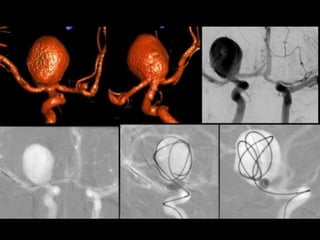

Aneurysm

Endovascular Treatments of Intracranial

Aneurysms

3-Endosaccular Embolization :

a) Technique

a) Technique :

-Coil embolization is performed under general

anaesthesia so the patients can be adequately

monitored and immobilized

-Selective catheterization of the aneurysm sac is

performed after systemic anticoagulation (by bolus

injection or infusion of heparin) and packing is

usually performed by placing large initial coils into

which smaller coils are packed

5-Adjuvant Endovascular Treatments :

-Coil embolization for a minority of aneurysms isn’t

possible because of their anatomy

-The features that make a particular aneurysm

uncoilable are :

a) Wide neck

b) Extreme size

c) Branch arteries arising from within the sac

d) Fusiform shape

-Stent & Coils and Flow Diverters

a) Stent & Coil :

-Placing a stent in the parent artery is a logical solution

to the problem of retaining coils in sessile very wide-

necked aneurysms

-Initially , the combined use of coils and stents was

confined to treatments of unruptured aneurysms

because of the need to place patients on antiplatelet

drugs (in addition to periprocedural heparin) as

prophylaxis against thrombosis within the stent

b) Balloon-Assisted Coiling :

-Balloon-assisted coiling (BAC) which is also known

as (the remodelling technique) involves

placement of a suitably sized compliant balloon

across the aneurysm neck during coil deployment

, the balloon is used to retain coils within the

aneurysm to compress their profile at the neck

(i.e. remodelling) and to be available to arrest

blood flow should rupture occur during

embolization

c) Flow Diverters :

-Flow diverters have been developed to treat

intracranial aneurysms

-These endovascular devices are placed within

the parent artery rather than the aneurysm

sac

-They take advantage of altering hemodynamics

at the aneurysm / parent vessel interface

resulting in gradual thrombosis of the

aneurysm occurring over time